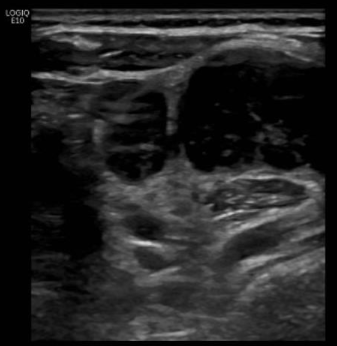

Objetivación de conglomerado adenopático con 2 adenopatías predominantes redondas de 2 cm, bien delimitadas, con hilio periférico y vascularización en hilio. Tiroides normal, bazo e hígado normales sin LOEs.

Uso de sonda lineal, proyección transversal: adenopatía redondeada con hilio periférico bien delimitada que no capta Doppler; y longitudinal: varias adenopatías, 2 de ellas más grandes, donde se objetiva la vascularización limitada al hilio.